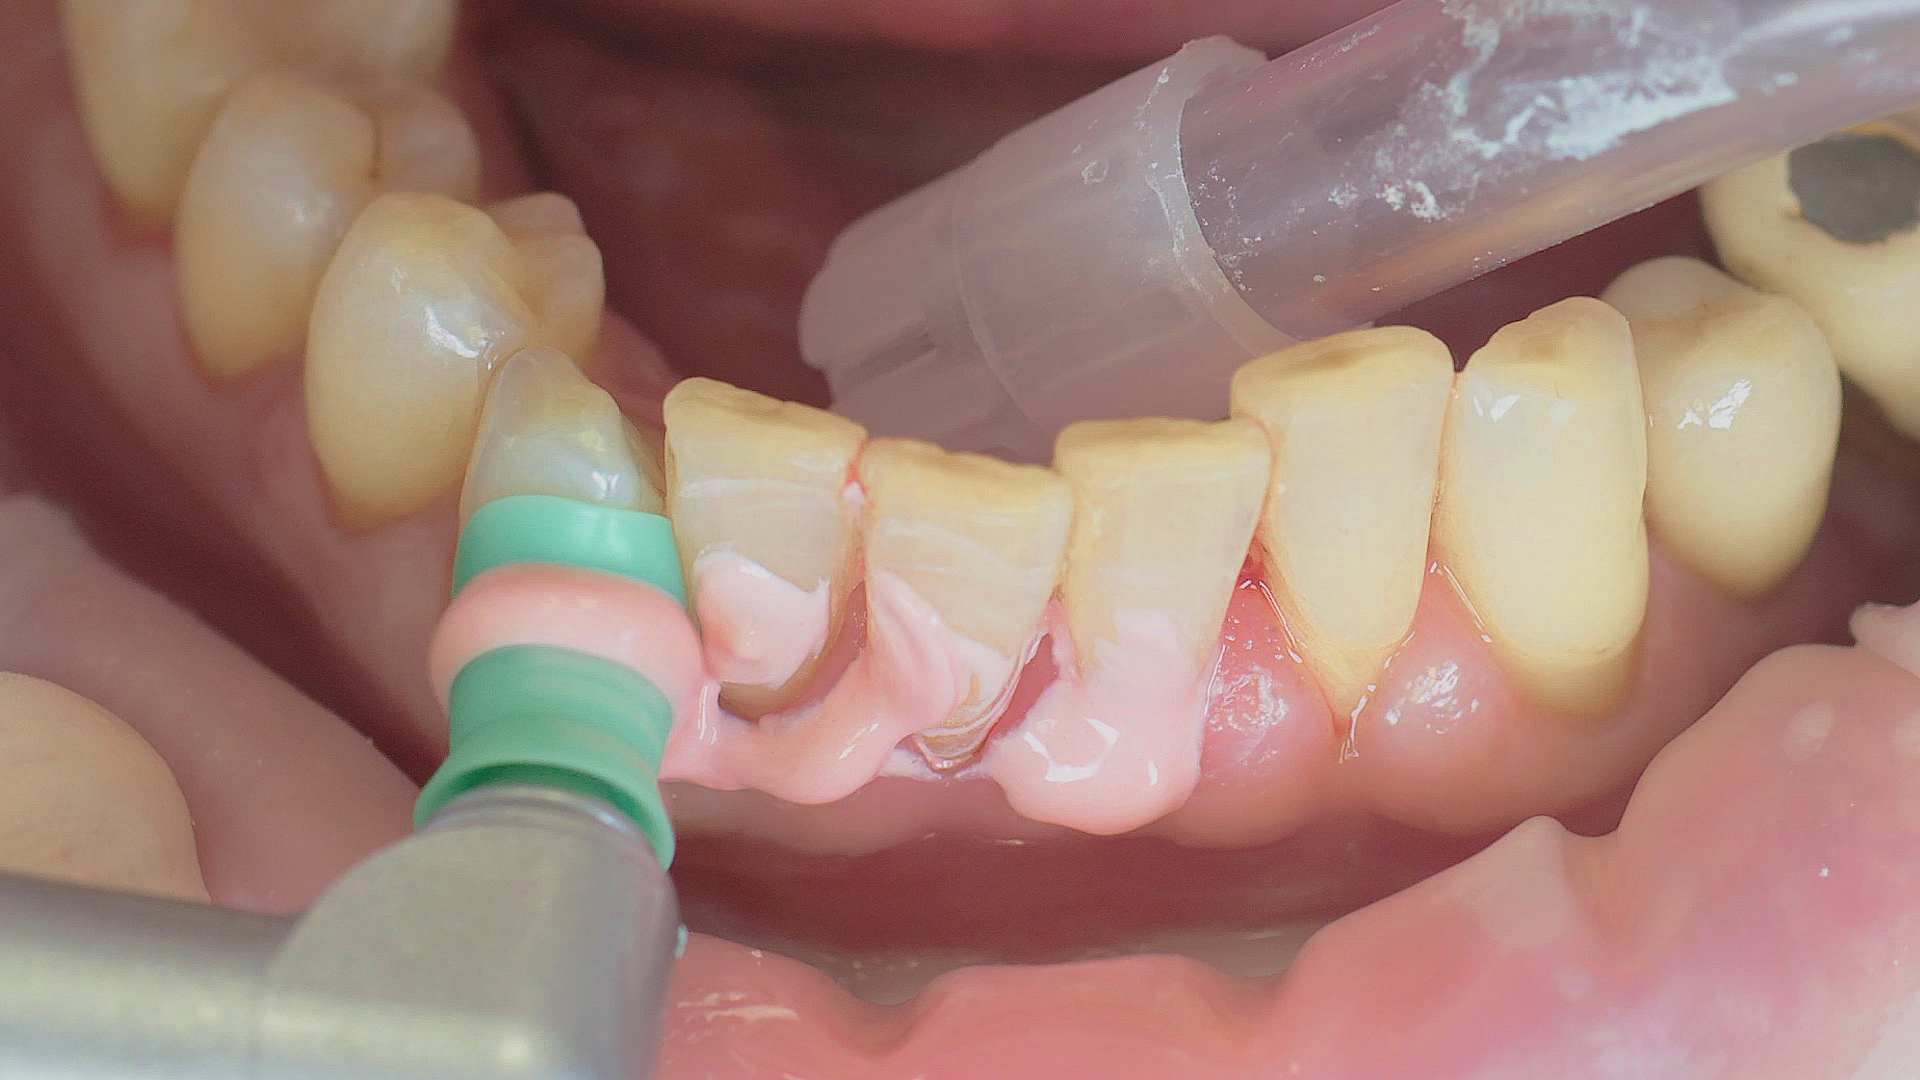

Where necessary, initial periodontal treatment is carried out. First, professional tooth cleaning establishes healthy gingival conditions. In this procedure, calculus (Fig. 1) and biofilm (Fig. 2) are removed as far as the gingival sulcus. In combination with careful instruction on oral hygiene, this gives the patient the basis for long-term freedom from inflammation.15

Calculus removal using an ultrasound

Fig. 1: Calculus removal using an ultrasound (W&H Tigon+ with a 3U tip) is a key part of professional tooth cleaning.